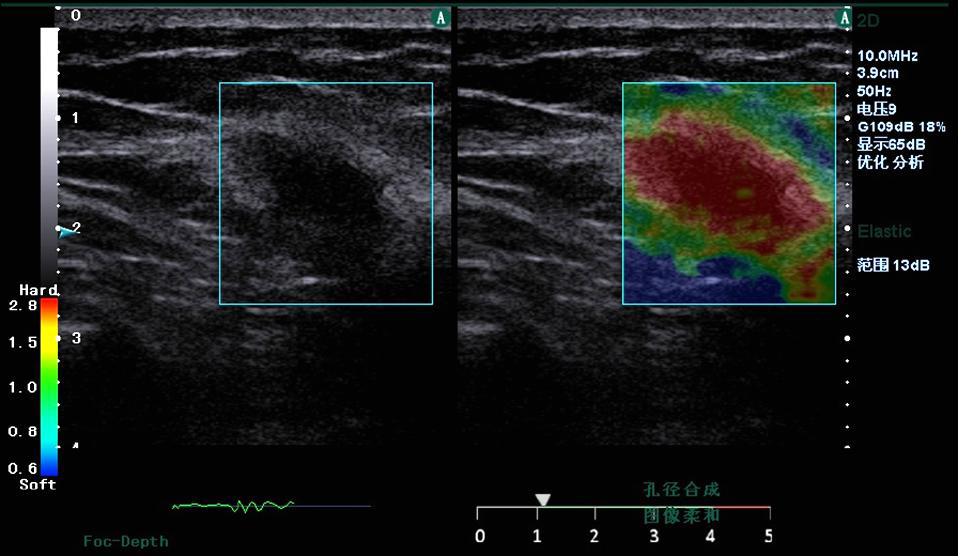

Figure 3. Clinical strain images of confirmed (a) inflammation lesion; (b) benign and (c) malignant breast tumor

2. Freehand elastography

Motion tracking of manual compression or breathing

induced movement generates a strain image

representing the elasticity of the underlying tissue. Statemed